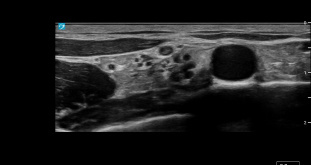

Metacarpal Head Cartilage Damage in Rheumatoid Arthritis 15836

Image

The Use of Ultra-High Frequency Ultrasound for Vascular Access in Paediatric Patients 15830